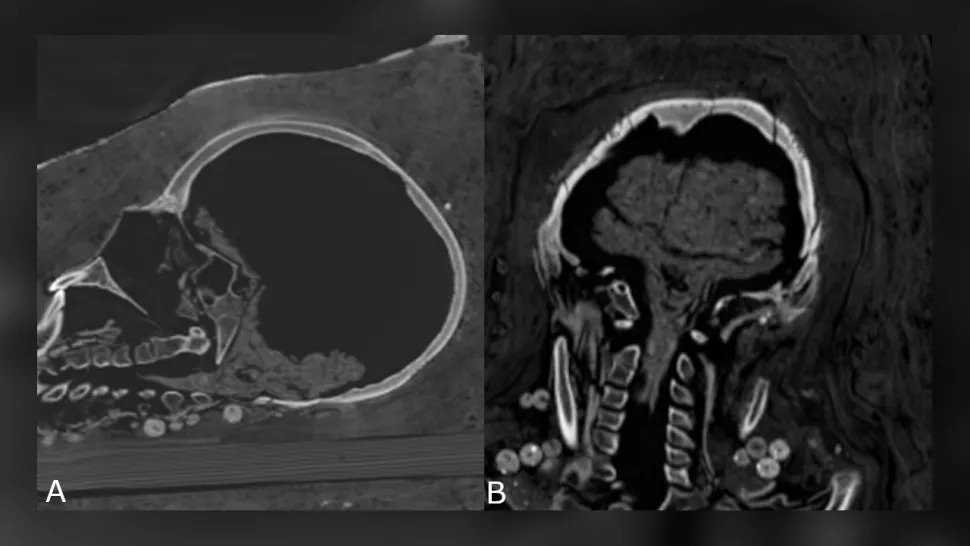

A nő agyát sem őrizték meg, de a kamasz agya megmaradt – összezsugorodott, de az agy és az agytörzs még mindig azonosítható volt -, és a serdülő többi belső szerve is jelen volt.

Zsugorodó tini agy. (Zesh és mtsai., PLOS One, 2020)